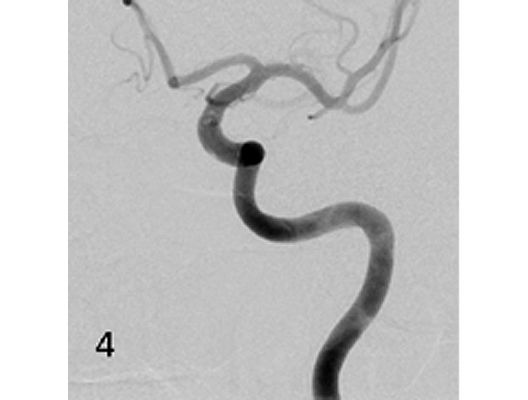

Mit den modernen Verfahren zur Wiedereröffnung von verschlossenen Blutgefäßen können wir Patienten mit Schlaganfall in vielen Fällen helfen. Das folgende Beispiel zeigt die angiographischen Bilder eines Patienten, der mit vollständiger Lähmung der rechten Körperhälfte und einer schweren Sprachstörung eingeliefert wurde. Ursächlich zeigte sich ein Verschluss der linken Halsschlagader, vermutlich auf dem Boden einer arteriosklerotischen Einengung (Bild 1). Das Gefäß wurde daraufhin mit einem Stent wiedereröffnet (Bild 2). Zusätzlich zeigte sich ein Verschluss der Endstrecke des Gefäßes durch Blutgerinnsel (Bild 3). Diese konnten vollständig entfernt werden (Bild 4). Der Patient erholte sich nach der Behandlung innerhalb weniger Tage vollständig.

Das Beispiel zeigt die angiographischen Bilder einer Patientin, bei der es zu einer Sehstörung gekommen war. Die Ursache war ein großes Aneurysma der Halsschlagader an der Schädelbasis (Bild 1). Bild 2 zeigt die Lage des Aneurysmas hinter dem Auge. Durch den Druck des Aneurysmas auf den Sehnerv war es zu der Sehstörung gekommen. Die Patientin wurde mit einer speziellen Gefäßprothese versorgt, welche über eine Punktion der Leistenarterie in die Halsschlagader eingesetzt wurde (Bild 3). Bei der Kontrolle nach 6 Monaten zeigte sich ein vollständiger Verschluss des Aneurysmas (Bild 4). Die Sehstörung hatte sich vollständig zurückgebildet.